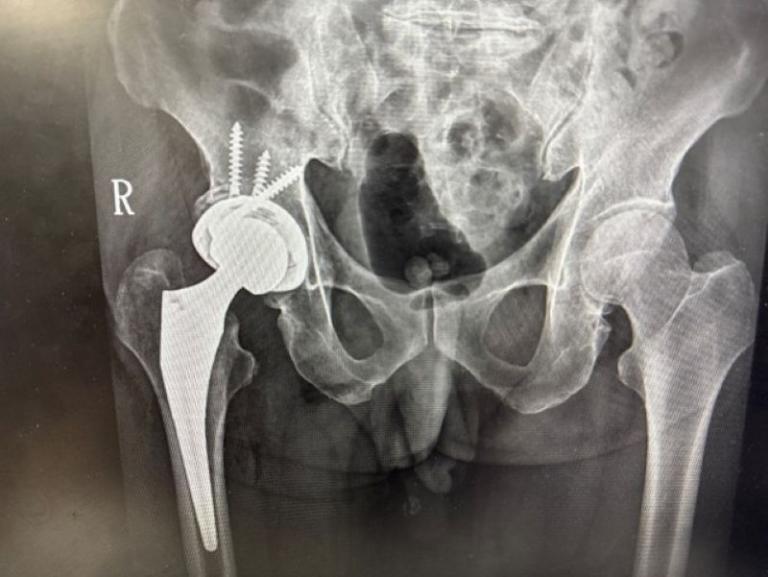

一名76歲老翁多年前因髖臼骨折接受手術,術後留下垂足與步態異常,造成長期行動不便,導致外傷性退化性髖關節炎,連上廁所與行走都成為挑戰,經新竹臺大分院骨科團隊詳細評估並與病人充分溝通後,決定採用「

前側入路(DAA)」人工髖關節置換手術,避開之前的手術區域,病人術後當天即可床邊如廁並下床行走,疼痛顯著減輕,展現微創技術在高齡手術中的安全與高效,成功改善長年困擾。

賈維焯醫師說,DAA手術的最大優勢在於保留肌肉結構、縮小傷口並降低疼痛,使病人能於術後儘早下床活動

,加速恢復日常生活功能,DAA人工髖關節置換術是近年國際間發展成熟的微創技術,新竹臺大分院骨科團隊結合術前影像分析與精準定位系統,提高手術植入穩定性與下肢長短對位準確性,與傳統後側入路手術相比,DAA術式不僅可減少術後疼痛與出血,亦能縮短復健期並降低脫臼風險。